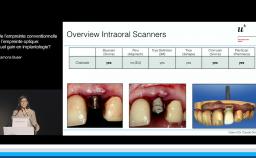

Au cours de cette présentation, le Dr Finelle nous montre tout l’intérêt du digital workflow dans une réhabilitation implantaire en secteur esthétique. Ainsi, à chaque étape de celle-ci, le numérique peut intervenir : au cours du diagnostic, de la chirurgie, de l’empreinte ou encore au cours de la réalisation prothétique.

Au travers de plusieurs cas cliniques, il nous est montré comment différents outils numériques permettent de préparer et d’obtenir une réhabilitation esthétique optimale. Au final, le digital workflow va apporter précision, prédictibilité, facilité de reproduction des formes dans la réhabilitation prothétique implantaire ; c’est également un formidable moyen de communication avec le patient.